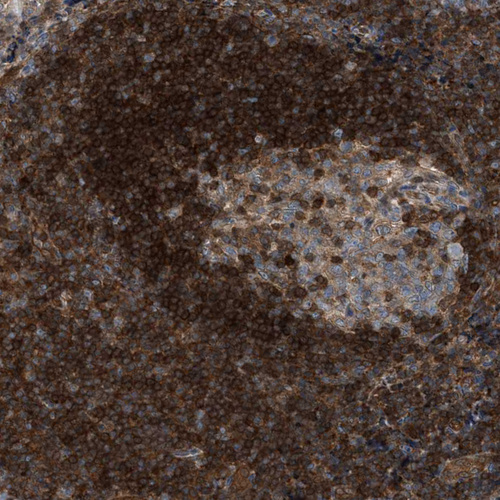

Immunohistochemical staining of human tonsil shows strong cytoplasmic positivity in non-germinal center cells.